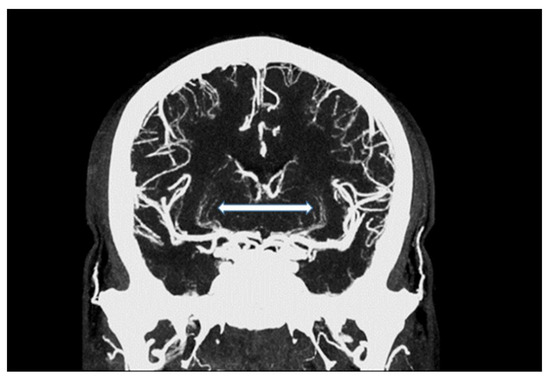

Figure 2.

Maximum intensity projection of an intracranial UHR-CTA, depicting traceability of lenticulostriate arteries (LSA; white arrow).

We were able to show that excellent image qualities were generated even though radiation exposure could be kept at explicitly moderate levels [10]. In addition, the occurrence of Hounsfield artefacts that frequently hinder the assessment of the vertebrobasilar system and the brainstem were also considerably low, enabling an advanced image interpretability. Both quantitative and qualitative evaluation of the UHR-CTAs confirmed our hypothesis of a highly remarkable improvement in image quality and spatial resolution. In particular, a high vascular contrast and a distinctly defined demarcation of the extracranial as well as the intracranial vessels could be demonstrated. It is noteworthy that even the smallest perforating arteries (e.g., LSA, as shown in Figure 3) vascularizing the deep brain structures become diagnostically accessible by UHR-CTA, which is generally not the case when using conventional CTA.